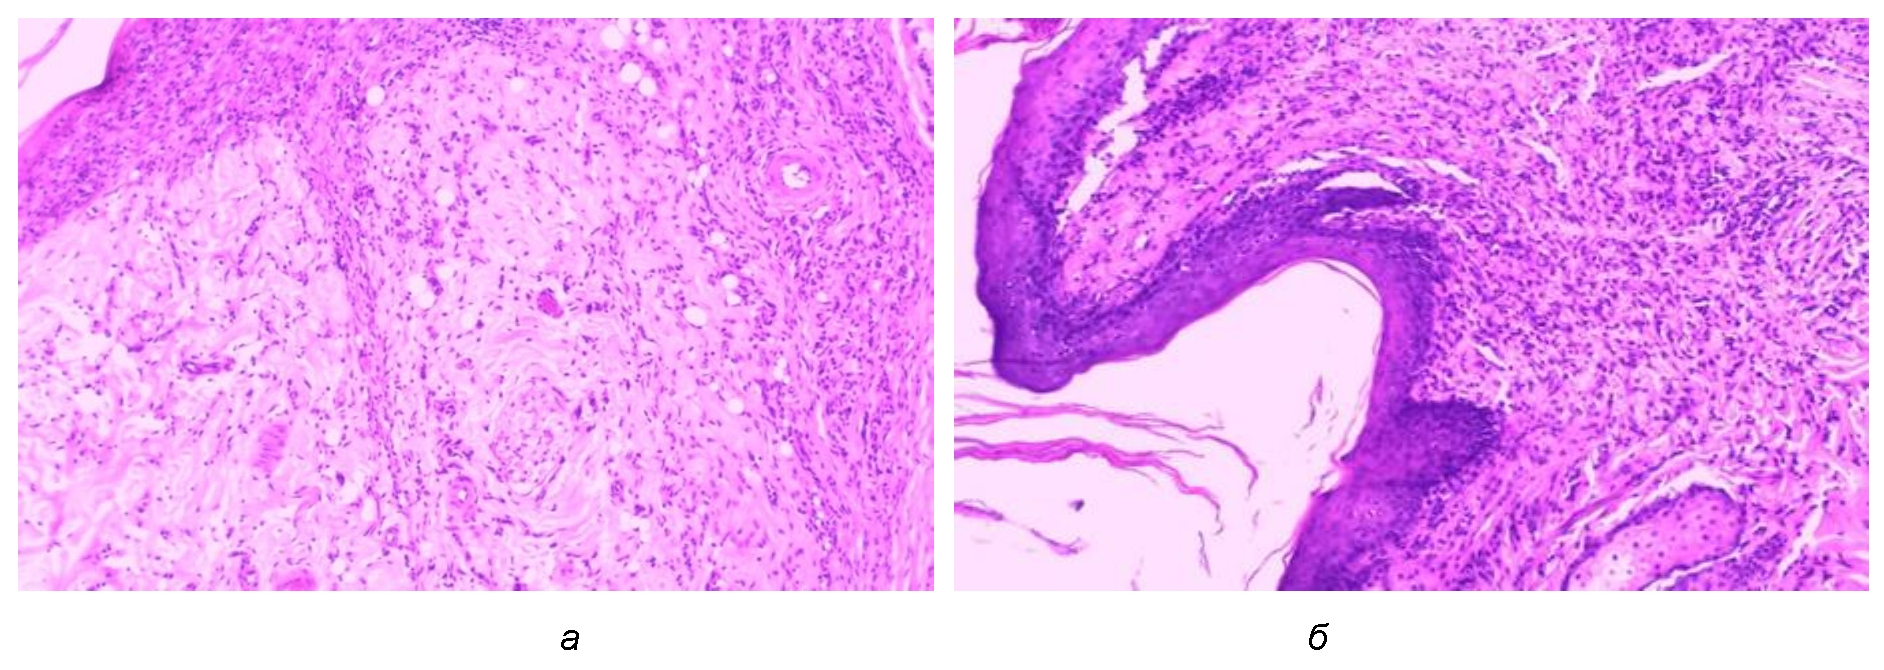

На 7-сутки эксперимента у старых крыс в группе с моделированной раной при гистологическом исследовании образцов тканей из ран выявлено наличие раневой поверхности с нек-ротизированными тканями в виде детрита и струпа. В краях раны отмечены очаги размножения эпителиальных клеток эпидермиса. Под струпом в сосочковом слое дермы определялись межклеточные отек, явления экссудации, наблюдалось значительное количество нейтро-фильных лейкоцитов, большинство из них были с признаками фагоцитоза. В дне раневого дефекта определялись очаговые кровоизлияния (рис. 1). У всех крыс данной группы в краях раны в дерме на 7-е сутки обнаружена грануляционная ткань с большим количеством соединительнотканных клеток: нейтрофильных лейкоцитов, фибробластов, гистиоцитов, лимфоцитов, небольшим количеством коллагеновых волокон.

В группе старых крыс с экспериментальным сахарным диабетом 2-го типа и с моделированной раной обнаружено наличие раневой поверхности с некротизированными тканями в виде детрита и струпа. В эпидермисе участки разрастания и регенерации по краям раны менее выраженные, чем у контрольных животных той же возрастной группы. Под струпом определяются нейтрофильные лейкоциты, признаки фагоцитоза выражены меньше, что, по нашему мнению, отражает нарушение в системе антиоксидантной защиты и сопровождается снижением уровня NO и активных форм кислорода, которые вырабатываются этими клетками [5]. Возможное снижение выработки NO в фазу пролиферации может способствовать снижению синтеза коллагена [6]. В более глубоких отделах ран отмечено наличие экссудата, обильная инфильтрация полиморфно-ядерными лейкоцитами и гистиоцитами, которые расположены диффузно, часть из них – периваскулярно, что, по-видимому, свидетельствует о повышенной проницаемости сосудистой стенки, способствующей поддержанию воспаления. В интиме кровеносных сосудов отмечены признаки повреждения эндотелия. Наблюдается появление коллагеновых волокон, наличие грануляционной ткани, незначительная эпителизация (рис. 1).

Рис. 1. Структурные изменения в области раневого дефекта: а – I группа: моделированная рана крысы в возрасте 24 мес. на 7-е сутки опыта; б – II группа: моделированная рана крысы в возрасте 24 мес. с СД2Т на 7-е сутки эксперимента. Окраска гематоксилином и эозином. Ув. ×100